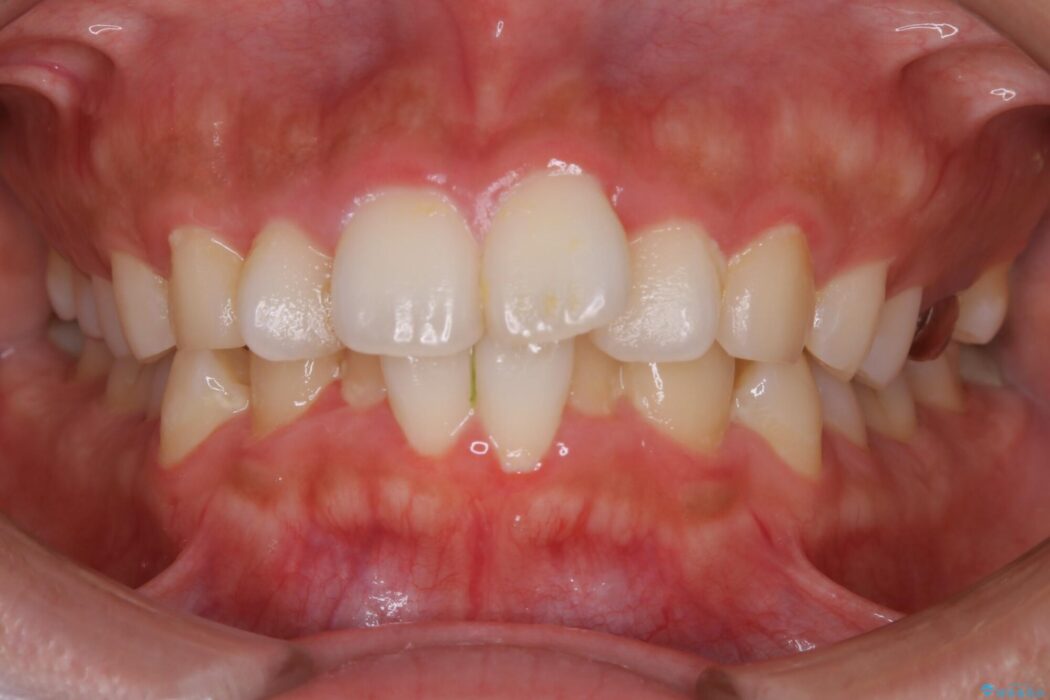

前歯のガタつきの治療を目的に来院されました。

主訴としては矯正治療にて歯列を整えることでした。